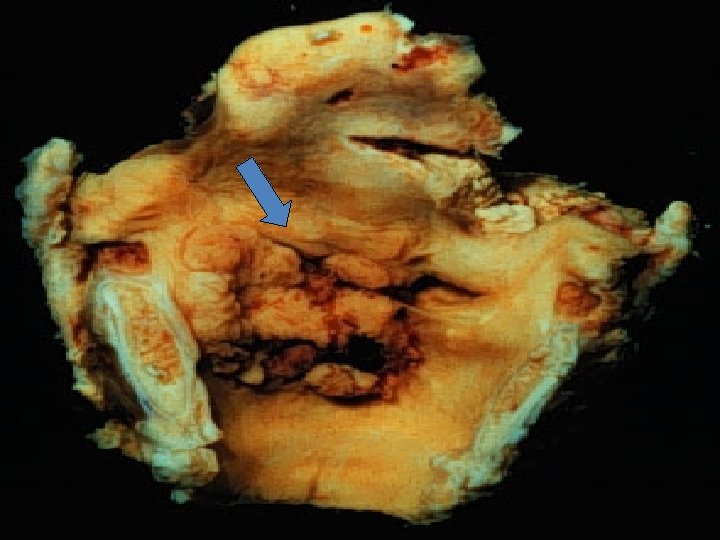

II. Carcinoma of larynx: Form less than 2% of all cancers. Age: more than 40 years, Male more than female. Etiology: 1. HPV. 2. Alcoholic. 3. Asbestos. 4. Radiation. All these causes are result in mucosal hyperplasia, dysplasia & carcinoma in situ (early stages of neoplasia).

Types according to the sites: 1. Glottic carcinoma: (on the vocal cord), 60 -70% of cases. 2. supraglottic carcinoma: 25%. 3. subglottic less than 5% of cases. Gross: Wrinkled plaques, ulcerating, fungating mass. Mic: Glottic carcinomas are well to moderate differentiated squamous cell carcinoma.

Clinical features: persistent hoarseness of voice. Prognosis: • Glottic carcinomas are confined to the larynx (good prognosis), this is due to the fact that this area has sparse lymphatic supply. • Supraglottic carcinomas in one third of cases showing cervical lymph nodes metastases.